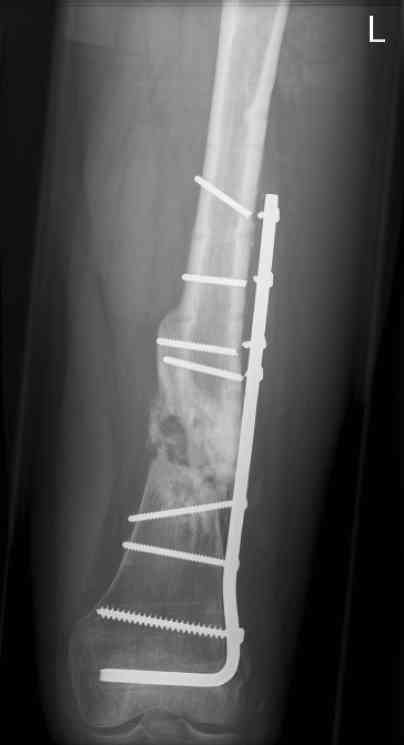

16 yr old boy, high energy motorcycle trauma trauma in July 2005 with:

- tibial shaft fracture L

july 05: LISS femur, LCP plate tibia, double recon. plate post. acetabulum

nov 07: persistant non-union distal femur; other fractures healed

uneventfully.

All with gradual/partial weightbearing etc. Currently 50-100% weight

bearing, no pain.